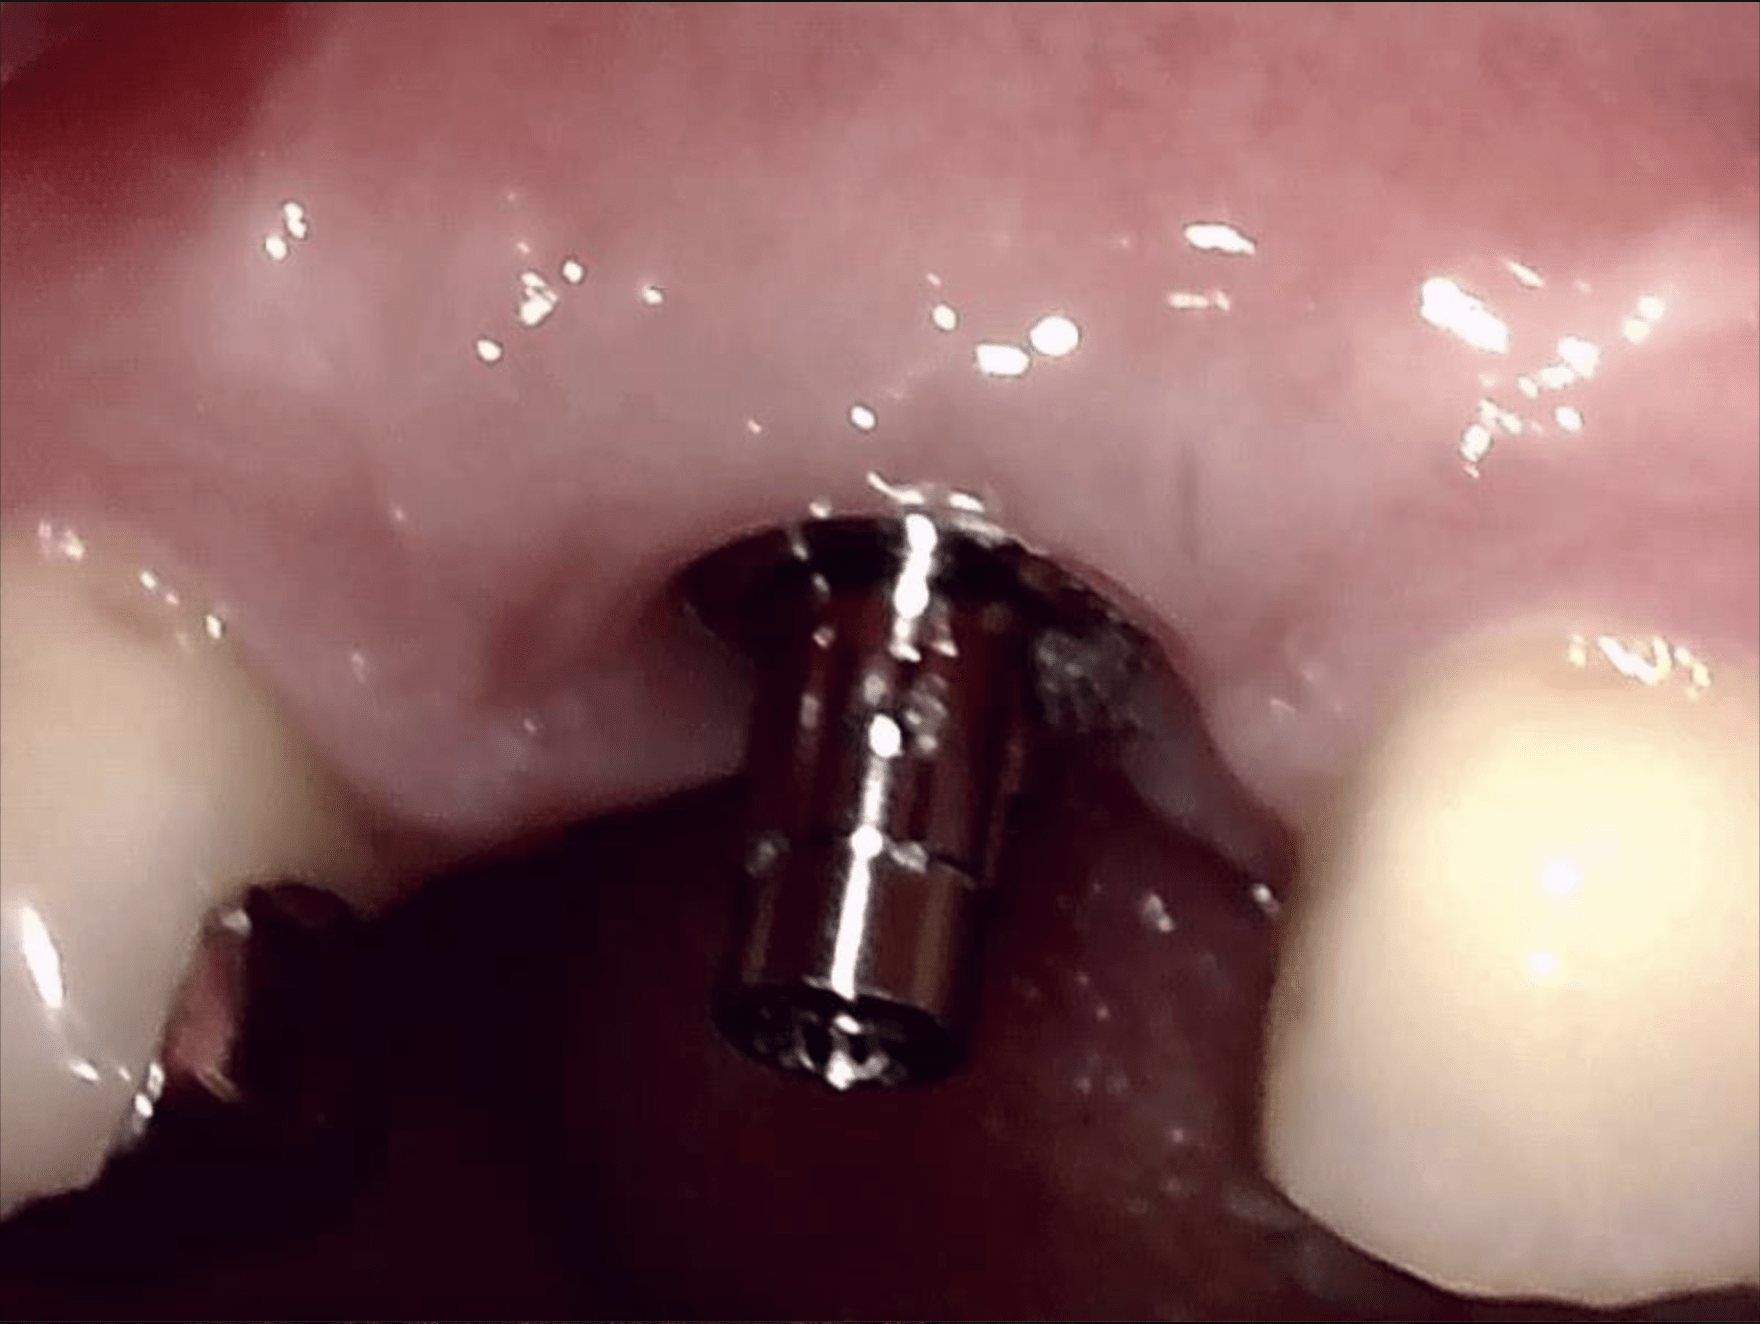

インプラント上部構造(最終的な本歯)の調整についてですが、スクリュー固定性の上部構造といいまして

ネジ止め式でアクセスホールがある上部構造の調整は結構難しいのです。

私は技工士と相談し、アバットメントと上部構造を分離して納品してもらうようにしました。